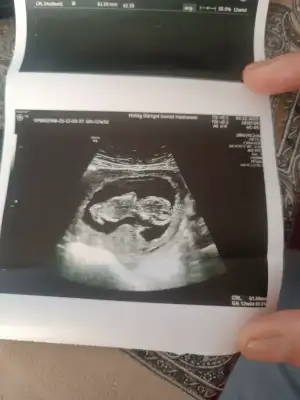

Merhaba arkadaşlar ben de haziranda doğum yapacağım ikili test yaptırdık bir problem çıkmadı fetal dna da yaptıracağız biz. Şu an 13+3 haftalık hamileyim ☺️ cinsiyet tahmini yapabilir misiniz ? Doktorumuz bir tahminde bulundu ama net bir şey diyemem dedi yüzdelik bile belirtmedi 10 ve 13. Haftalık fotoğraflarını bırakıyorum

Erkek